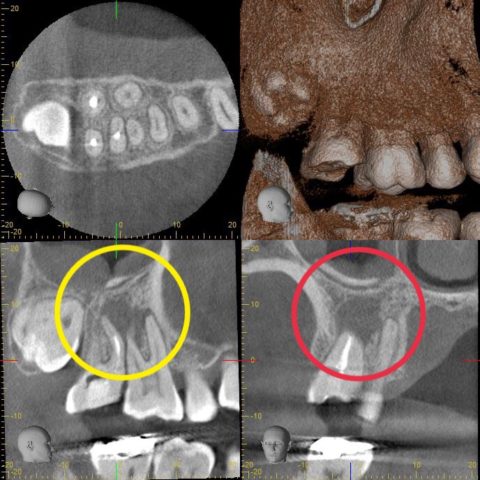

治療後に痛みがある根管治療/再根管治療外科治療

根管治療を行いその後、外科処置に移行した患者さん

メリット…上顎洞炎が治り、骨も再生する

デメリット…外科処置が必要となる為、全身疾患がある方は要相談 |